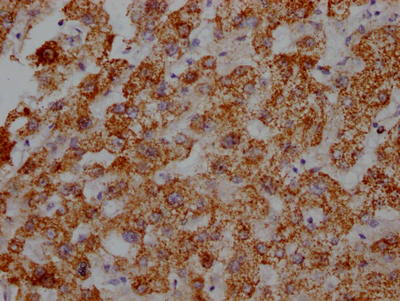

IHC image of CSB-RA216446A0HU diluted at 1:100 and staining in paraffin-embedded human heart tissue performed on a Leica BondTM system. After dewaxing and hydration, antigen retrieval was mediated by high pressure in a citrate buffer (pH 6.0). Section was blocked with 10% normal goat serum 30min at RT. Then primary antibody (1% BSA) was incubated at 4℃ overnight. The primary is detected by a Goat anti-rabbit IgG polymer labeled by HRP and visualized using 0.05% DAB.

IHC image of CSB-RA216446A0HU diluted at 1:100 and staining in paraffin-embedded human liver tissue performed on a Leica BondTM system. After dewaxing and hydration, antigen retrieval was mediated by high pressure in a citrate buffer (pH 6.0). Section was blocked with 10% normal goat serum 30min at RT. Then primary antibody (1% BSA) was incubated at 4℃ overnight. The primary is detected by a Goat anti-rabbit IgG polymer labeled by HRP and visualized using 0.05% DAB.